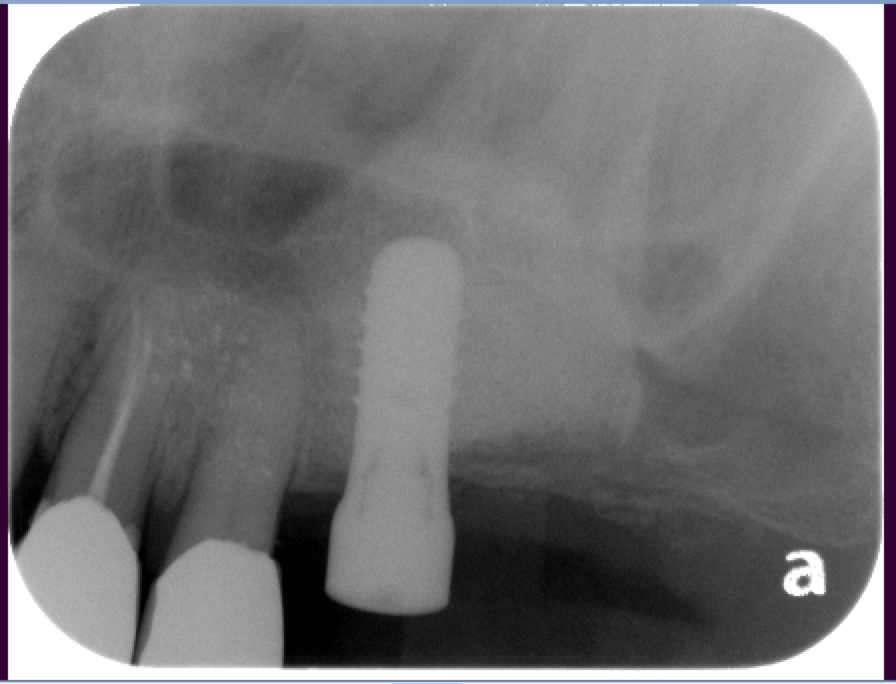

The bone used in a sinus lift may come from your own body (autogenous bone), from a cadaver (allogeneic bone) or from cow bone (xenograft). You will need X-rays taken before your sinus lift so the dentist can study the anatomy of your jaw and sinus. You also may need a special type of computed tomography (CBCT) scan. This scan will allow the dentist to accurately measure the height and width of your existing bone and to evaluate the health of your sinus.

Dental Implant Centre in Vancouver Burnaby Sinus Lift Dental implant Surgery Dr. Noroozi Implant Specialist IMPrESS Perio Implant Center.001

Sinus Lift, Bone Graft, Implants Dr. Noroozi IMPrESS Perio Implant Center